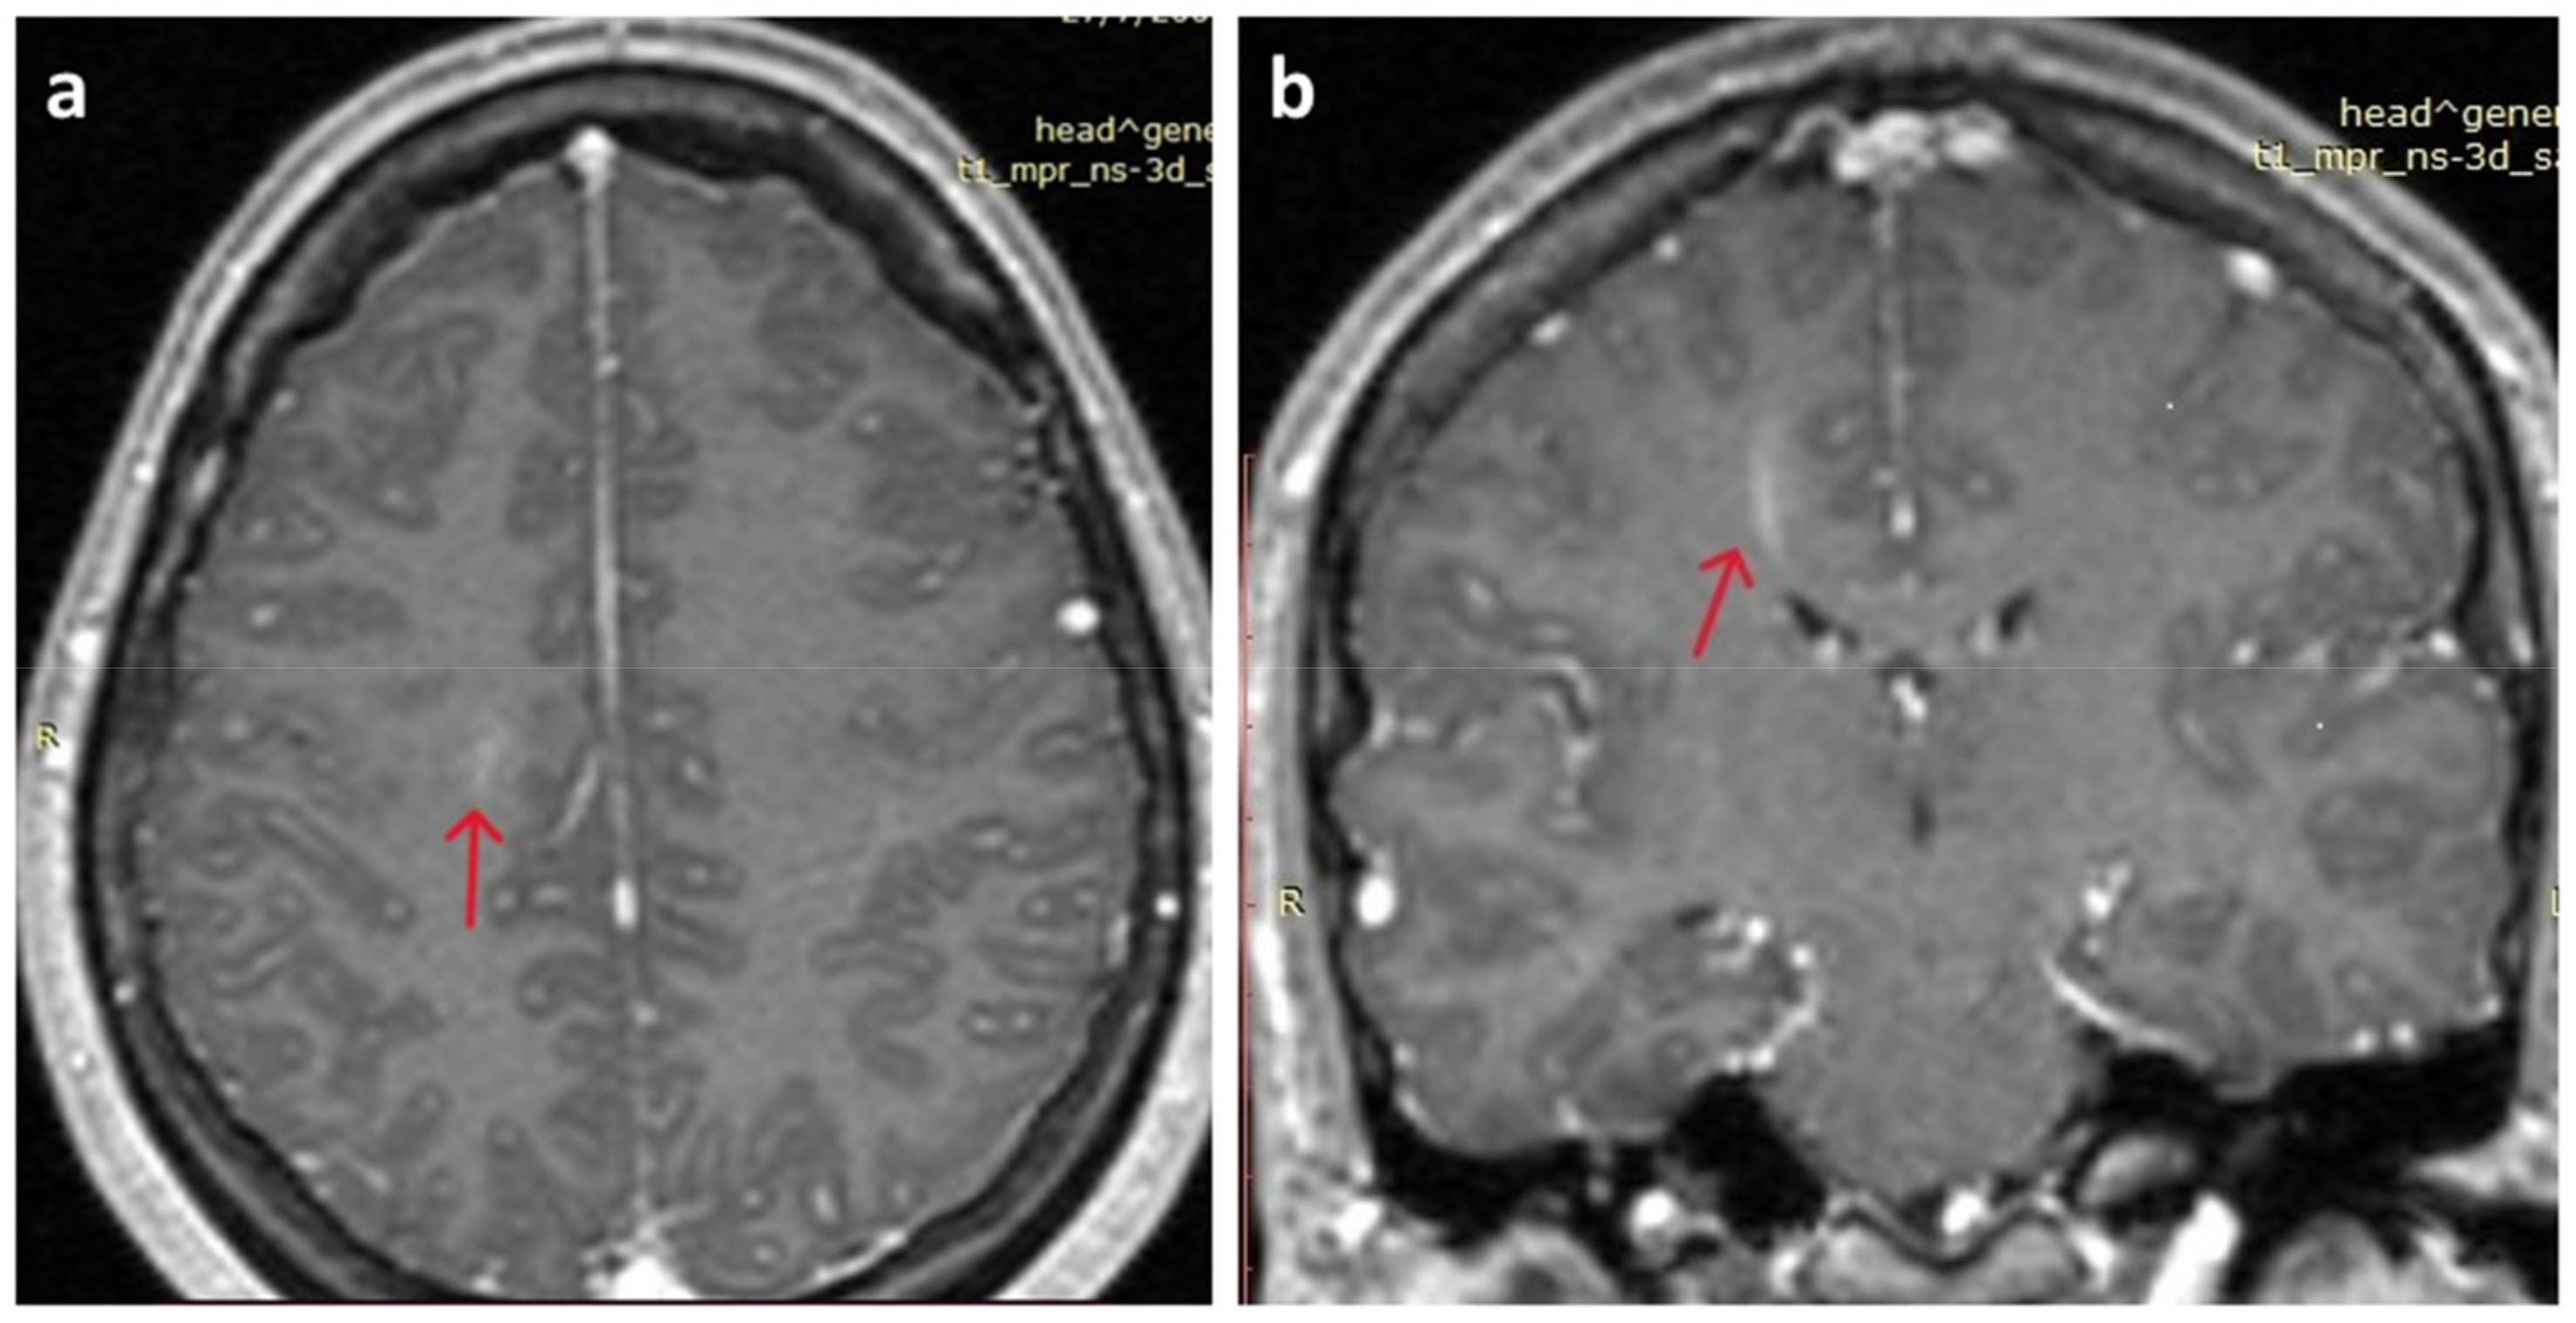

2. Detailed Case Description